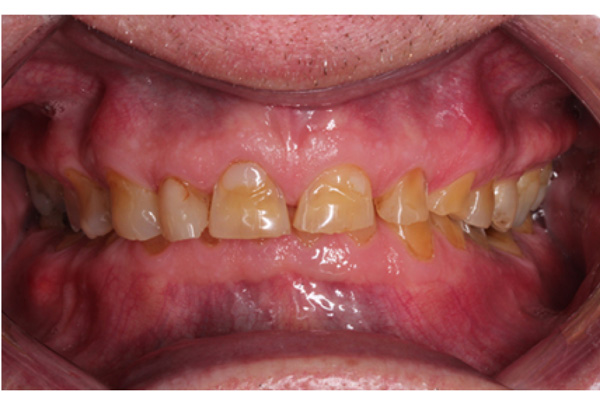

The patient presented with competent lips, an average lip line, normal TMJ function, and a mild Class II Division I incisor relationship with an increased overbite. The preoperative pan-oral radiograph is shown in Fig. (1). Boney exostoses and a large mandibular torus in the lower right mandible were present. The intra-oral presentation of the teeth is shown in Figs. (2-6). The patient had good oral hygiene and a healthy periodontium. The teeth had a glossy, smooth, and glazed appearance, showing cupping of the occlusal surfaces with significant loss of hard tissue and yellow color from the underlying dentine. This presentation was indicative of severe generalized tooth wear with exposed dentine in all sextants. The palatal, occlusal, and incisal surfaces were mainly affected, with lower buccal surfaces exhibiting more wear than the lower lingual, resulting in a reverse curve of Monson. The maximum BEWE score of 18 was recorded, meaning that the tooth with the most severe wear in each sextant had greater than 50% surface loss [9]. Several posterior teeth had amalgam restorations with defective margins (FDI 16, 26, 27, 37, and 47), as shown in Figs. (5 and 6). All teeth responded normally to pulp sensibility tests (cold test). The radiographs did not show any apical pathology to be present, but the pan-oral shows the scooped-out appearance of the lower molars.

IPS Empress Direct ® (Ivoclar Vivadent, Schaan, Liechtenstein) composite was syringed onto the worn surface and into the stent,which was seated onto the tooth. The composite was cured through the stent for 20 seconds; then the stent was removed, and the composite curing light was used again to ensure afull set for a further 40 seconds. The PTFE tape was removed, the excess composite at the gingival margin was trimmed back with narrow and ultra-fine diamond finishing burs, and a final polish was performed using Shofu Super-Snap Rainbow® discs (Kyoto 605-0983, Japan). The resultsare shown in Figs. (8-10). The slight increase in the vertical dimension is seen when comparing the pre-operative frontal image (Fig. 2) with the post-op image (Fig. 8), where some of the labial surfaces of the lower incisors is now visible, which was planned from the outset.